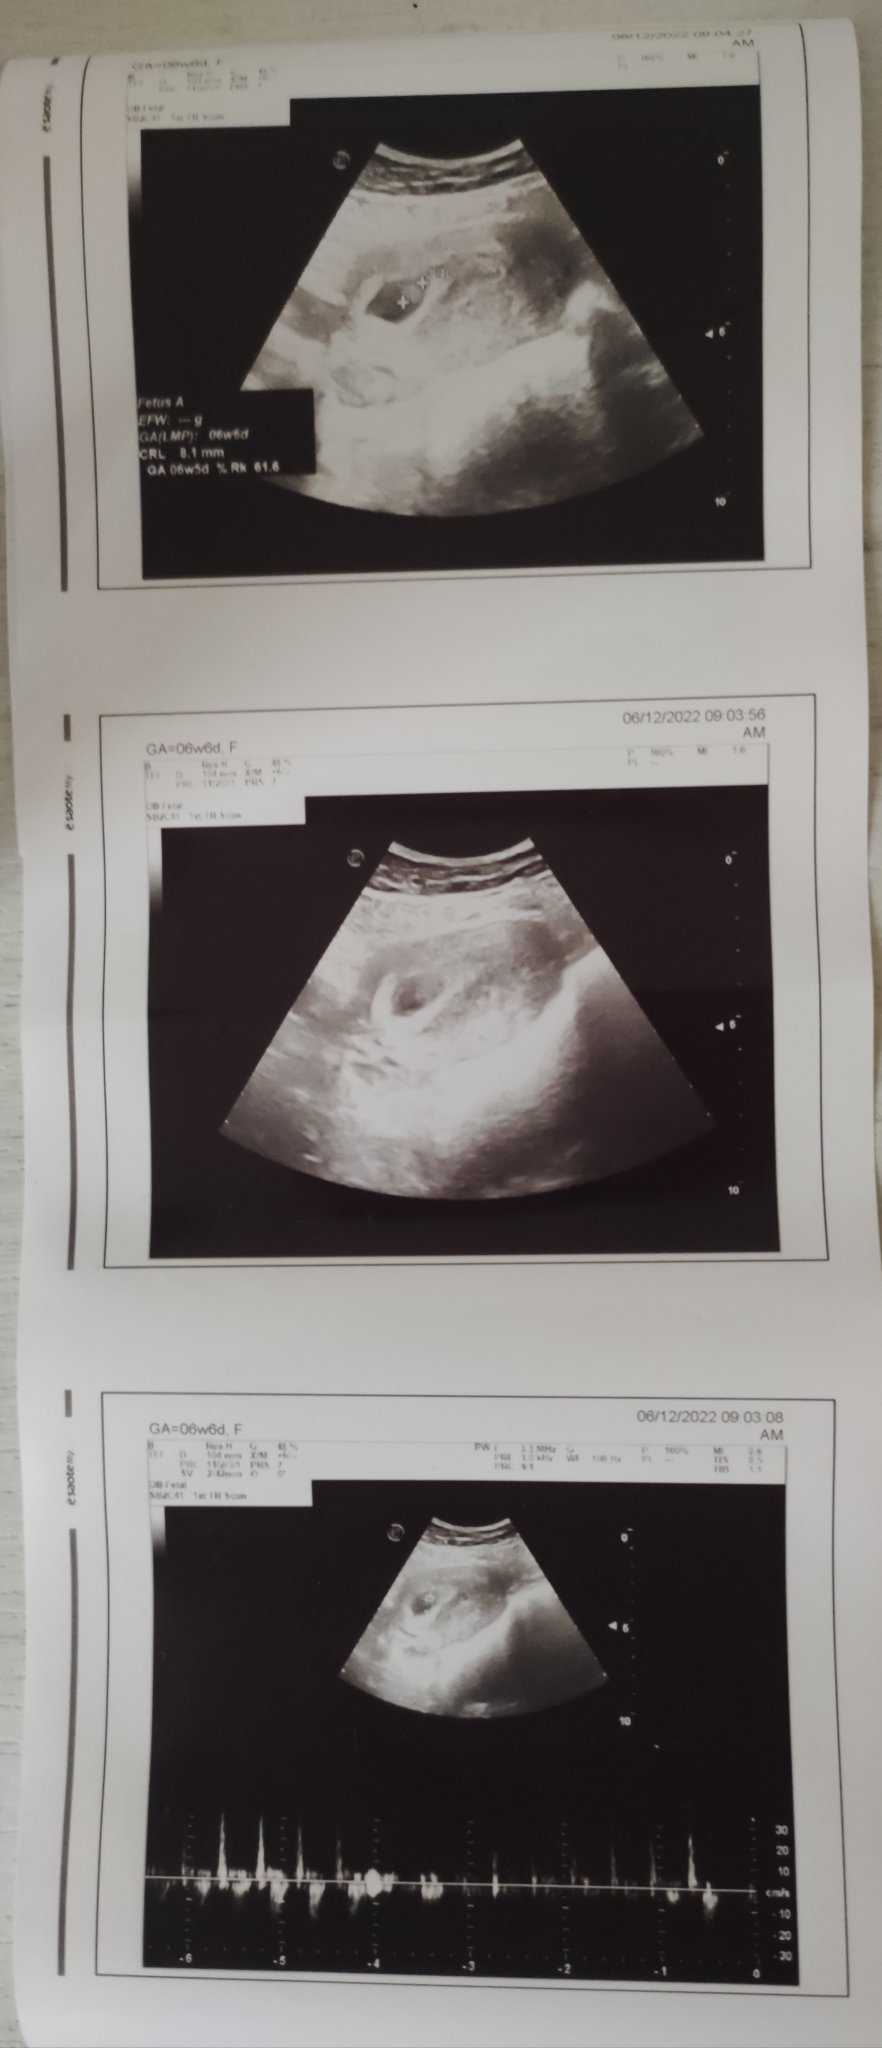

Здравейте Simple Smile и ние днес бяхме на преглед 6+6 г.с и чухме сърчицето ❤️ Всичко е наред, развива се нормално. 😊

Момичета,  връщам се и аз от доктор. Има бебе, има и пулс. Направо не мога да повярвам Heart след този кръвоизлив, че все още е там душичката Hug 6+2, отговаря си точно.

Какъв беше пулса на бебчето?